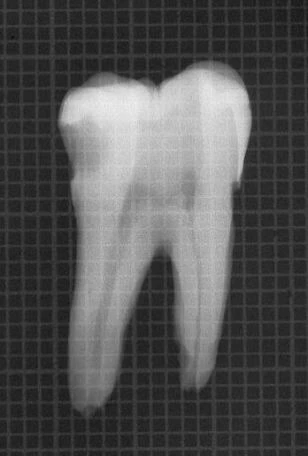

- Nếu khó tìm thấy ống tủy, không nên dùng đê cao su cho đến khi tìm được miệng ống tủy, cũng như trường hợp răng mọc lệch, chen chúc hoặc bị răng giả che hay những trường hợp ống tủy bị canxi hóa. Hình dạng và độ nghiêng của những răng gần đó, mô nướu và những cấu trúc mô cứng bao xung quanh chân răng cũng có thể giúp ích trong việc xác định những ống tủy chân răng. Khi đã mở xoang tủy và xác định được ống tủy, có thể đặt đê cao su (hình 3.15).

Hình 3.15. A. Phim răng cối lớn 1 hàm trên, chân răng gần ngoài bị cắt vì lý do nha chu. B. Mở lối vào ống tủy, tháo đê cao su để clamp không gây trở ngại cho việc chụp phim kiểm tra lỗ vào ống tủy. C. Dùng file 06 ở chân xa ngoài sau khi chân trong đã được tìm thấy, làm sạch và tạo hình. Nên tháo đê cao su để tiện cho việc kiểm tra ống tủy. Cán dụng cụ nên buộc vào chỉ nha khoa và buộc đầu chỉ còn lại bên ngoài. D. Đặt lại đê cao su và hoàn thành việc điều trị theo cách truyền thống. E. Phim sau điều trị. F. Sau 4 năm.